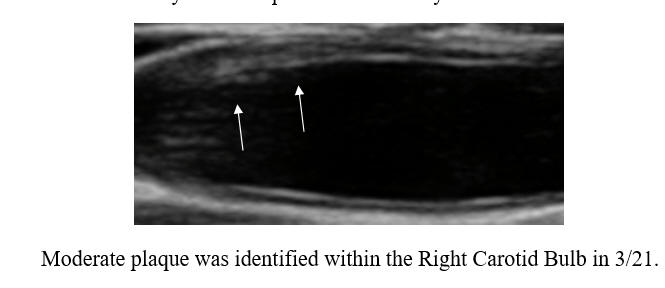

I began working with PM in '07, 14 years ago. Chest tightness, then associated with a non-threatening stress test, resolved following 20 IV EDTA treatments. PM's IMT of 0.678 was below-average-for-age; carotid plaque was not identified. PM began a program of risk factor reduction, but we could not dent PM's LDL elevation (150-180 mg/dl), at least not with treatments that PM could tolerate. PM's IMT rose between '08 and '22, at an average rate of 0.007 mm per year, but calcific carotid bulb plaque had developed over this interval. PM received two months of cyclodextrin in '23, as a proactive preventative, our theory being that if we can't lower PM's circulating lipids, perhaps we could make up by pulling lipids out of the vascular wall. PM's IMT was repeated in 1/25, and demonstrated active IMT regression, at a rate of 0.02 mm per year (a lot). Thus PM's predisposition towards plaque formation was reversing, and of greater importance to PM, we observed plaque regression. The right carotid bulb plaque, which had developed over 14 years, decreased in size over two years! Our plan, going forward, will be for PM to complete two moths of cyclodextrin every year, with a repeat carotid study in 2-3 years.